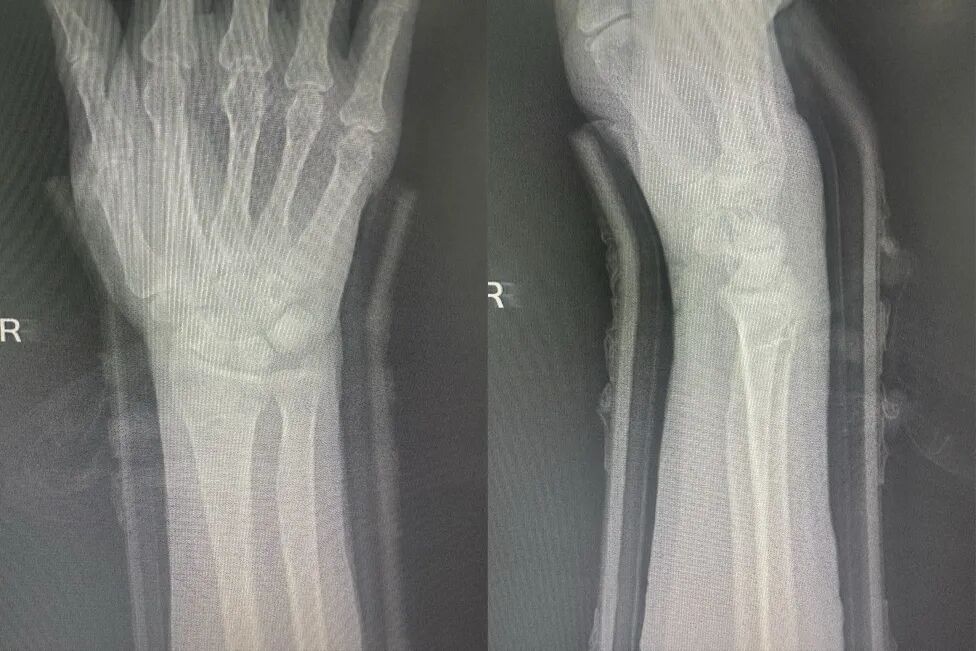

复位后

治疗后,赵军详细指导患者进行手指抓握、肩肘活动等功能锻炼,并叮嘱定期复查调整夹板松紧。一周后复查,患者肿胀消退,X光显示其骨折对位良好。